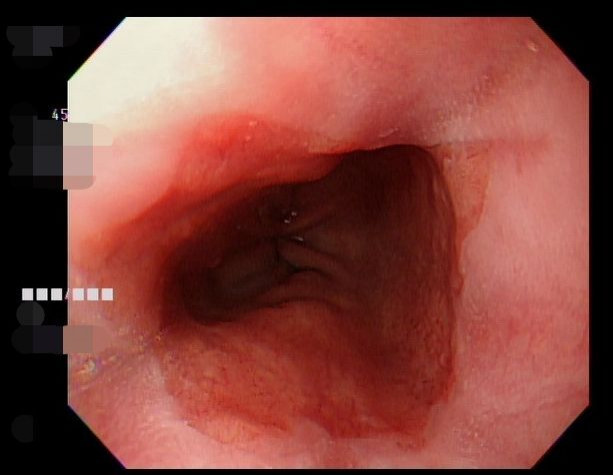

亞洲大學附屬醫院肝膽腸胃科醫師江承源指出,許男妻子陪同就醫時指出丈夫每晚睡覺時打呼聲大,偶爾還會出現短暫喘不過氣的停頓,患者也描述最近幾週屢屢在夜裡被胸口灼熱、喉嚨胃食道逆流驚醒,擔心身體出狀況趕緊就醫。經詳細問診與評估後,確診為「夜間型胃食道逆流」,因合併打呼與白天精神不濟等狀況,研判也罹患睡眠呼吸中止症。

江承源解釋,夜間胃食道逆流多發生於平躺與肌肉放鬆的睡眠狀態,胃酸更容易逆流至食道,造成火燒心、胸悶或突然驚醒,部分患者還會伴隨心悸與恐慌感,感覺上很像心臟疾病,但多數情況其實並非心臟本身異常。

因此,一旦睡眠呼吸中止發作時,患者會因呼吸道暫時塌陷,患者會用力吸氣,造成胸腔內負壓增加,這股抽吸力容易把胃內容物往上拉,使胃酸逆流進入食道,形成夜間反覆驚醒與睡眠破碎的惡性循環。